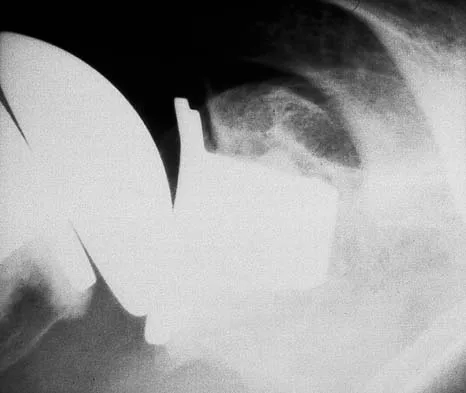

Figure 16 shows the radiograph of an otherwise healthy 62-year-old woman who fell. Management should consist of

Explanation